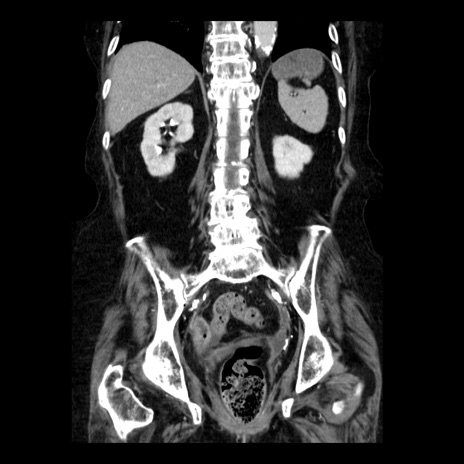

症例14(冠状断像)

【症例】 90歳代女性

【主訴】 腹痛・嘔吐

【現病歴】今朝から左側腹部痛を認めた。 経過観察していたが、嘔吐を認めたため来院。

【既往歴】 子宮癌術後

【身体所見】 意識清明、BP 127/54mmHg、P 98bpm Sp02 95%(RA)、BT 35.8°C、腹部平坦・軟腸ぜん動音聴取良好、右下腹部圧痛(+) 反跳痛なし

【データ】WBC 9800、CRP 0.46